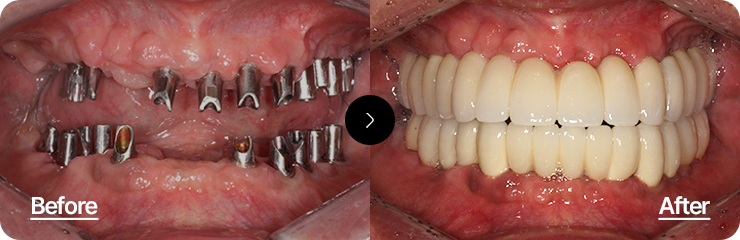

상실된 치아 전체를 복원하여

자연스럽고 건강한 구강 기능 회복

최소한의 임플란트로 최적의 위치에 식립하여 기능과 심미성을 동시에 회복하는 치료입니다.

정확한 교합 분석과 풍부한 임상 경험이 요구되는 고난이도 시술입니다.